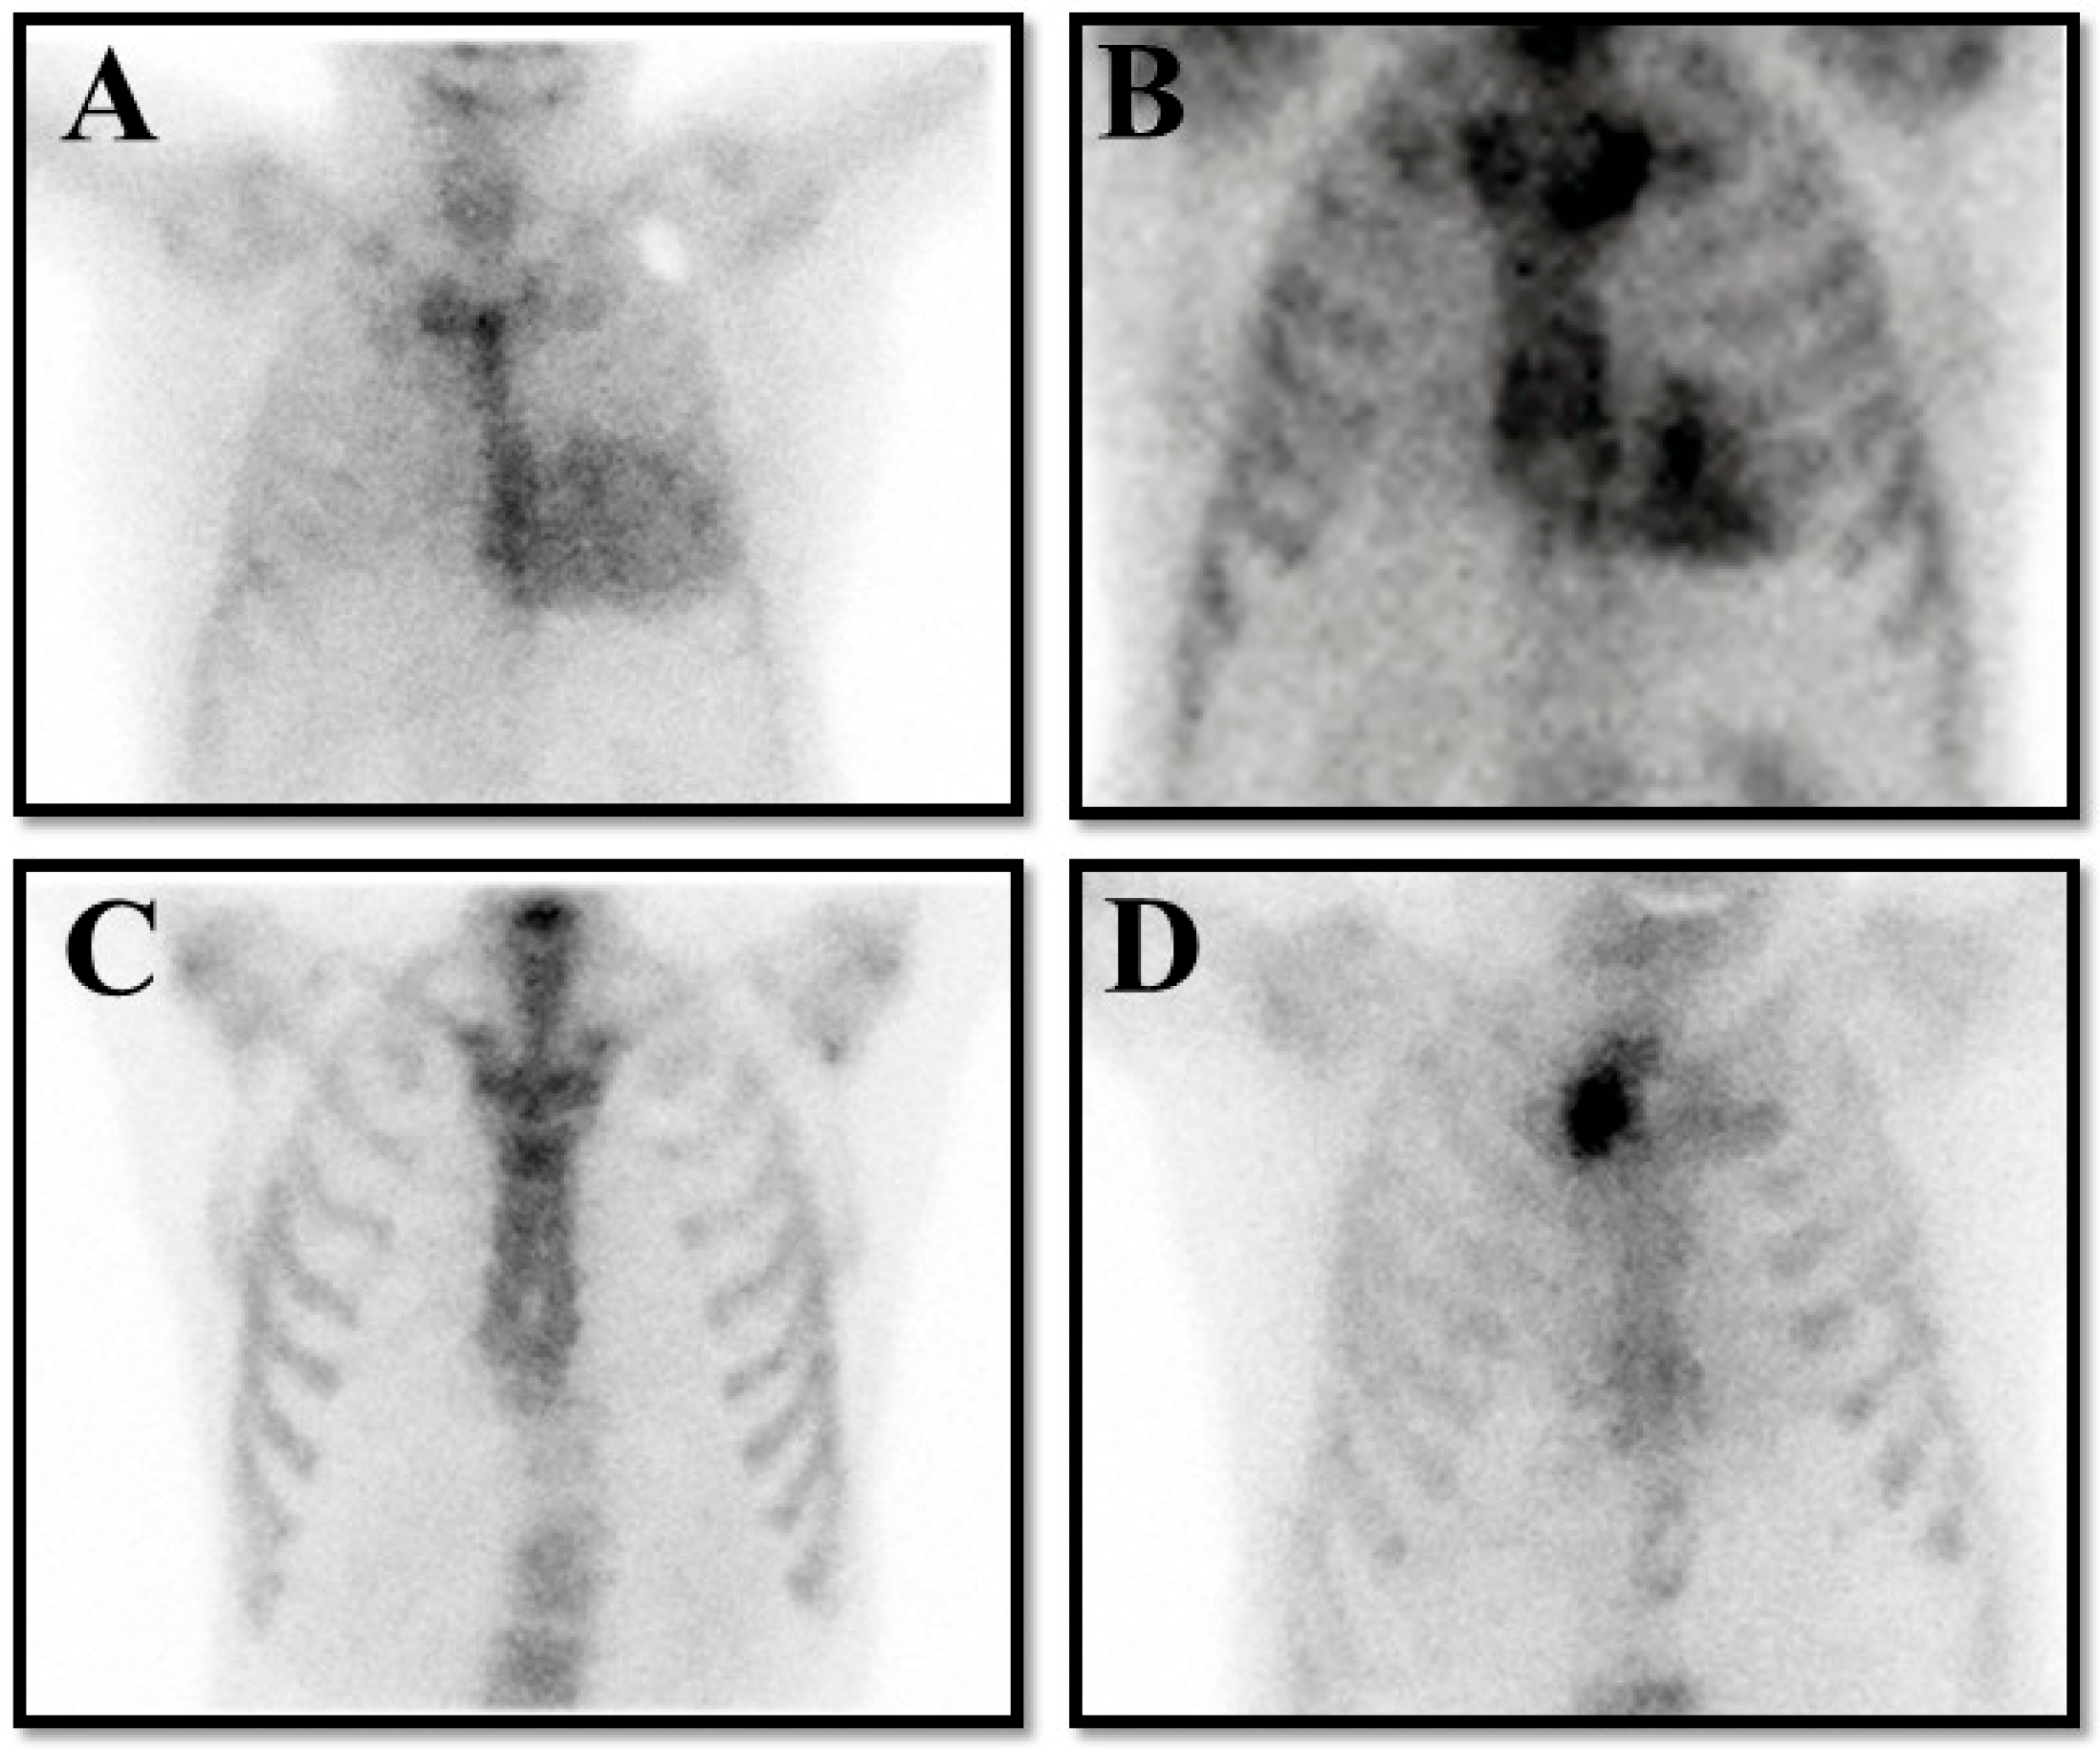

- Saro, R.; Pavan, D.; Porcari, A.; Sinagra, G.; Mojoli, M. Lights and Shadows of Clinical Applications of Cardiac Scintigraphy with Bone Tracers in Suspected Amyloidosis. J. Clin. Med. 2023, 12, 7605. [Google Scholar] [CrossRef] [PubMed]

- Singh, V.; Falk, R.; Di Carli, M.F.; Kijewski, M.; Rapezzi, C.; Dorbala, S. State-of-the-art radionuclide imaging in cardiac transthyretin amyloidosis. J. Nucl. Cardiol. 2019, 26, 158–173. [Google Scholar] [CrossRef]

- Gherghe, M.; Lazar, A.M.; Sterea, M.-C.; Spiridon, P.M.; Motas, N.; Gales, L.N.; Coriu, D.; Badelita, S.N.; Mutuleanu, M.-D. Quantitative SPECT/CT Parameters in the Assessment of Transthyretin Cardiac Amyloidosis—A New Dimension of Molecular Imaging. J. Cardiovasc. Dev. Dis. 2023, 10, 242. [Google Scholar] [CrossRef] [PubMed]

- Kessler, L.; Fragoso Costa, P.; Kersting, D.; Jentzen, W.; Weber, M.; Lüdike, P.; Carpinteiro, A.; Oubari, S.; Hagenacker, T.; Thimm, A.; et al. Quantitative 99mTc-DPD-SPECT/CT assessment of cardiac amyloidosis. J. Nucl. Cardiol. 2023, 30, 101–111. [Google Scholar] [CrossRef] [PubMed]